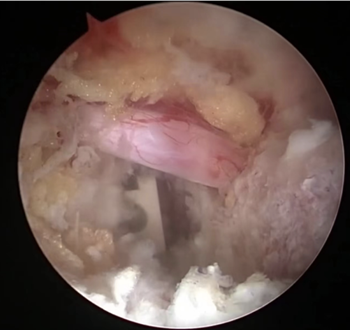

内镜下清晰可见神经根及融合器,手术安全有保障